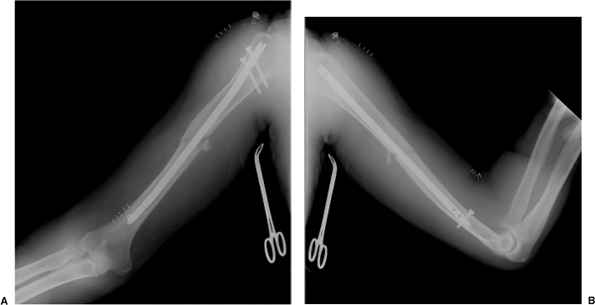

it will not be displaced in the soft tissues. Final AP and lateral

radiographs (Fig. 6.22) are taken in the operating room.

Figure 6.22. A. Final AP and (B) lateral radiographs after antegrade nailing.